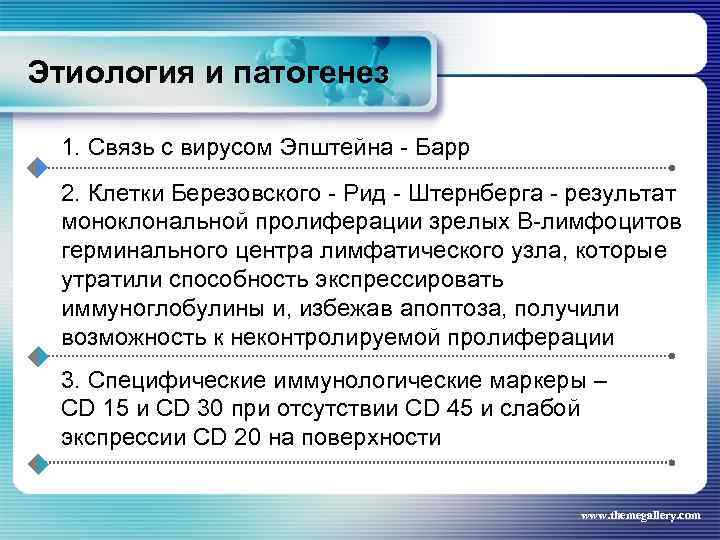

Этиология и патогенез 1. Связь с вирусом Эпштейна - Барр 2. Клетки Березовского - Рид - Штернберга - результат моноклональной пролиферации зрелых В-лимфоцитов герминального центра лимфатического узла, которые утратили способность экспрессировать иммуноглобулины и, избежав апоптоза, получили возможность к неконтролируемой пролиферации 3. Специфические иммунологические маркеры – CD 15 и CD 30 при отсутствии СD 45 и слабой экспрессии CD 20 на поверхности www. themegallery. com

Этиология и патогенез 1. Связь с вирусом Эпштейна - Барр 2. Клетки Березовского - Рид - Штернберга - результат моноклональной пролиферации зрелых В-лимфоцитов герминального центра лимфатического узла, которые утратили способность экспрессировать иммуноглобулины и, избежав апоптоза, получили возможность к неконтролируемой пролиферации 3. Специфические иммунологические маркеры – CD 15 и CD 30 при отсутствии СD 45 и слабой экспрессии CD 20 на поверхности www. themegallery. com